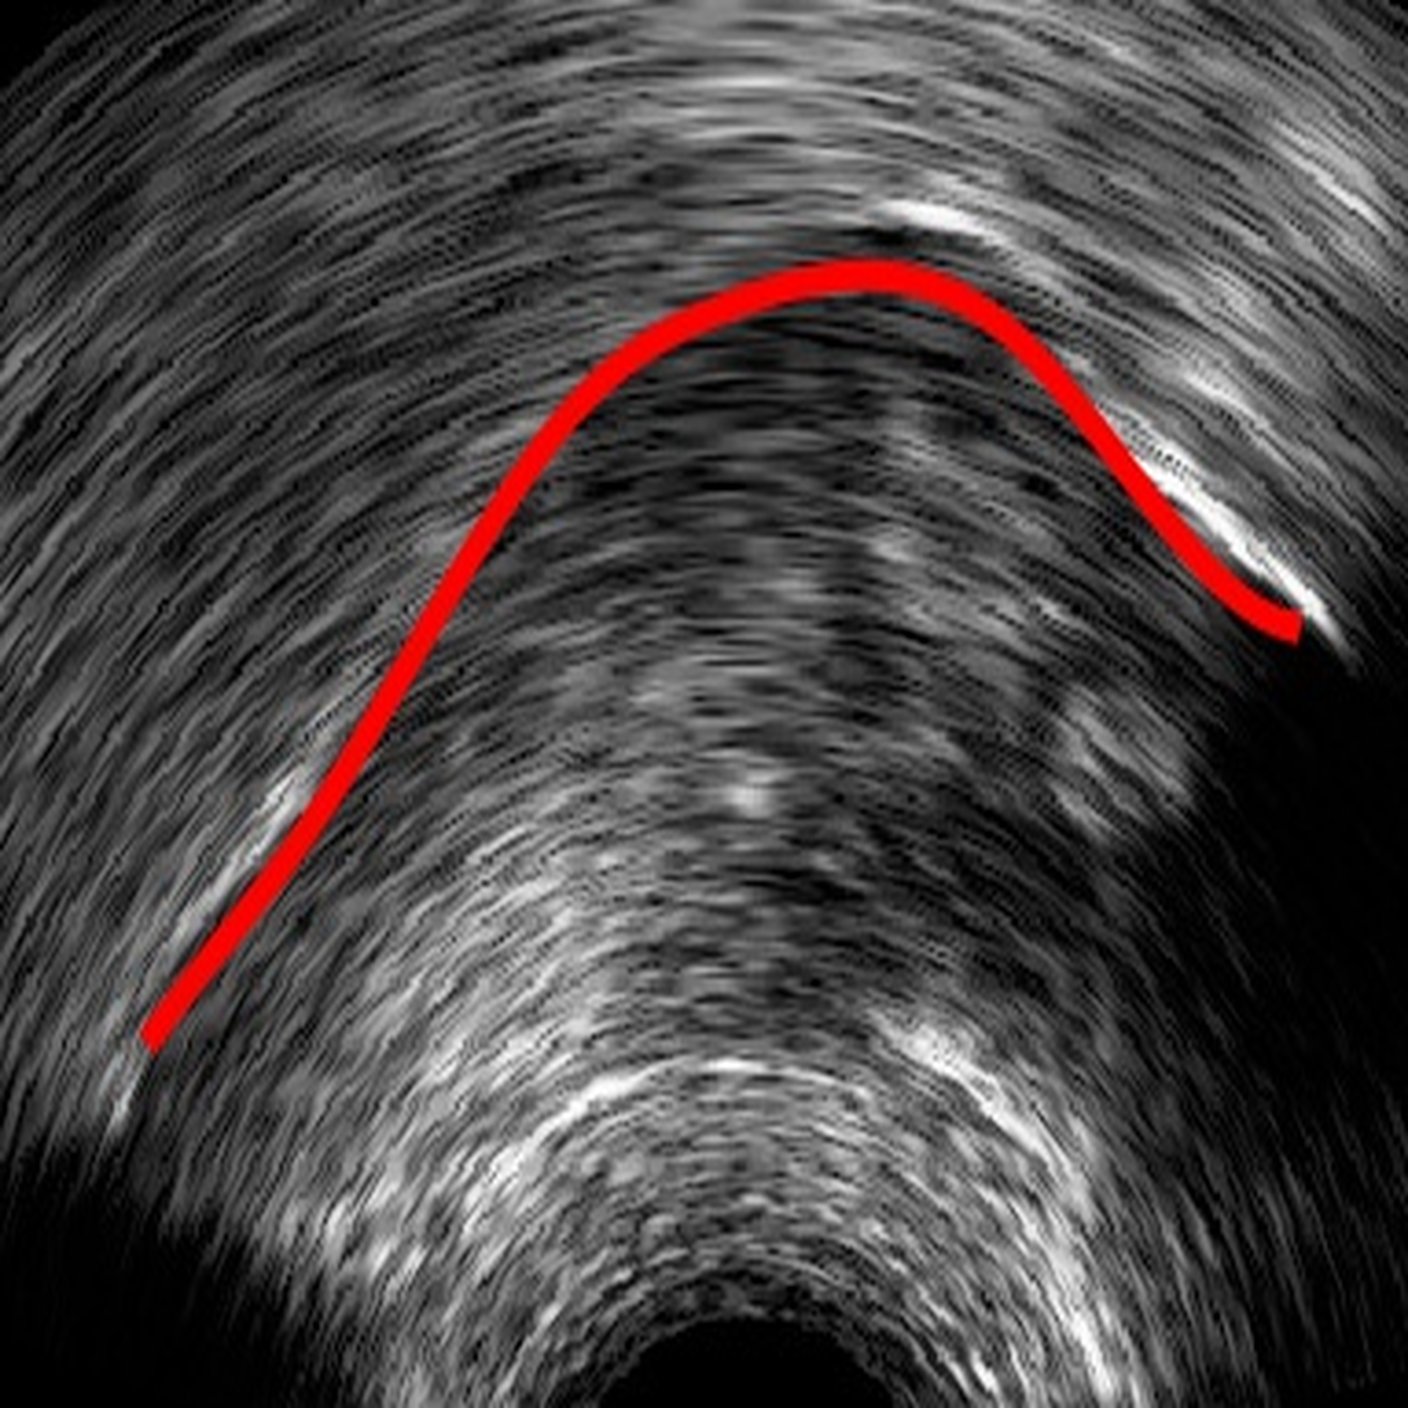

Ultrasound tongue imaging provides a non-invasive means for assessing tongue position and movement during speech production. However, the presence of speckle noise and irrelevant high contrast edges often degrades the usability of ultrasound images by obscuring the tongue surface [1]. Consequently, extracting tongue contours from ultrasound images remains a non-trivial task.

6 Error analysis

As the CNN is trained to identify the white edges directly corresponding to the tongue surface, additional or missing white edges due to bad image quality or speaker physiology can lead to failures in identifying parts of the tongue surface. In the absence of prior knowledge of plausible tongue shapes, the model will sometimes generate tracking errors when the white edge becomes blurry or interrupted. Similarly, bright edges in the image background are likely to be recognized as part of the tongue; tongue contours generated from image frames with these edges will likely suffer from implausible curvatures as interpolation in post-processing attempts to connect these regions. There some potential solutions to these problems, including incorporating temporal constraints on tongue contour variations across frames [3], or adding a smooth constraints that penalizes discontinuity of tongue contours, or introducing a strong prior probability of possible tongue locations. In data processing, these issues can also be mitigated by tuning the parameters in post-processing to match the needs of the specific dataset, and remaining errors can also be addressed through manual correction (as even then, the workload is considerably reduced relative to manually labeling all frames).